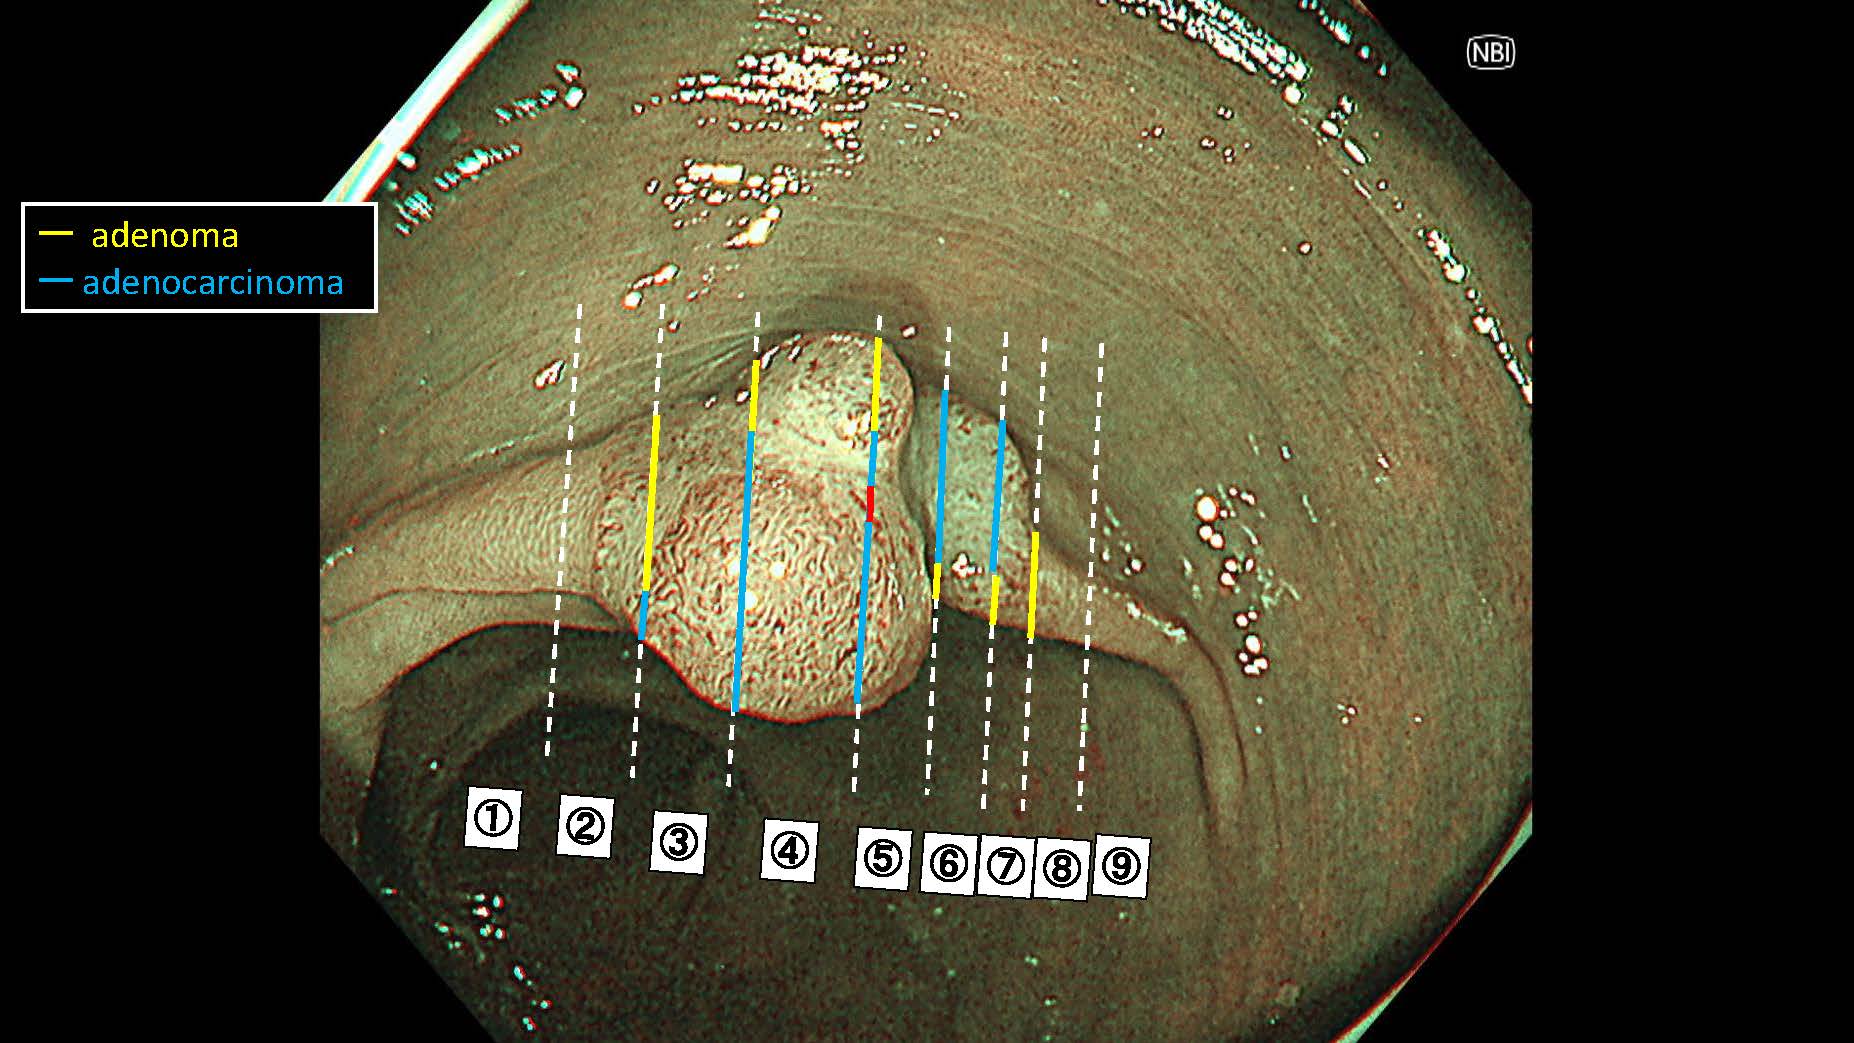

消化管Mapping~大腸~ 2025.6.11

内視鏡検査・治療

消化管Mapping